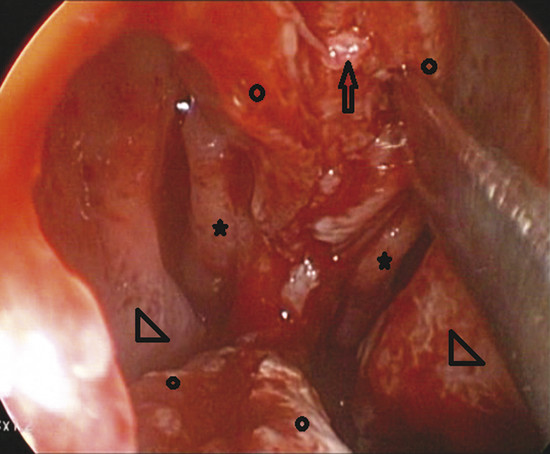

Vicryl 4/0 sutures are used to fix the graft in place within the tunnel. The first stitch is made posteriorly by taking one bite about 5 mm posterior to the posterior edge of the perforation and the other bite into the graft. The graft is then approximated to the perforation and tucked into place as the stitch is tightened (Fig. 9‑3).

The graft is positioned between the mucoperichondrium of both sides and between the mucoperichondrium and the cartilage of the one side. The graft is fixed by more stitches positioned superiorly, inferiorly, and anteriorly (Fig. 9‑4, Fig. 9‑5).